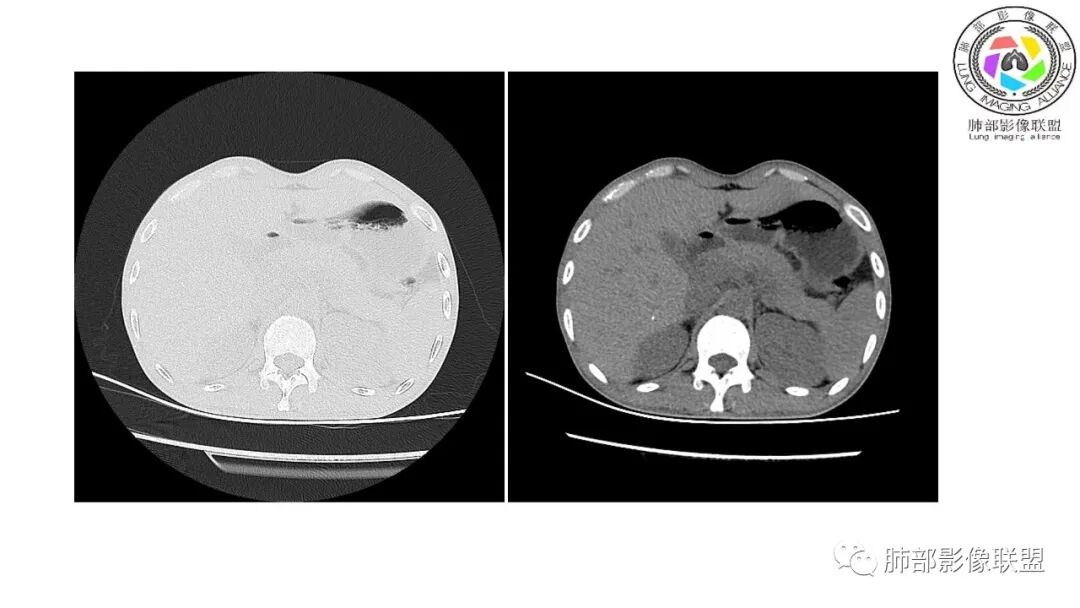

以下为2021-7-15日上腹部CT

影像与临床:1.青年男性,HlV阳性,颜面部皮疹(未提供皮疹图像)、发热(高热),实验室CRP、PCT高,T-Spot阴性。2.右肺下叶空洞结节,壁厚不均,边界清楚,其内线状影,未见液平及钙化,未见卫星灶,纵隔淋巴结增大,双侧腋窝见增大淋巴结。心腔内低密度提示贫血可能。肝脾影增大,未见结节影及块影。腹膜后见多发增大淋巴结。

综合分析:本例肺部影像学改变并不具有特征性,空洞性病灶须与多种疾病鉴别,但年轻HIV阳性患者,高热,皮疹,肝脾增大,纵隔、腋窝、腹膜后见多发增大淋巴结等都强烈提示马尔尼菲篮状菌感染的可能性。